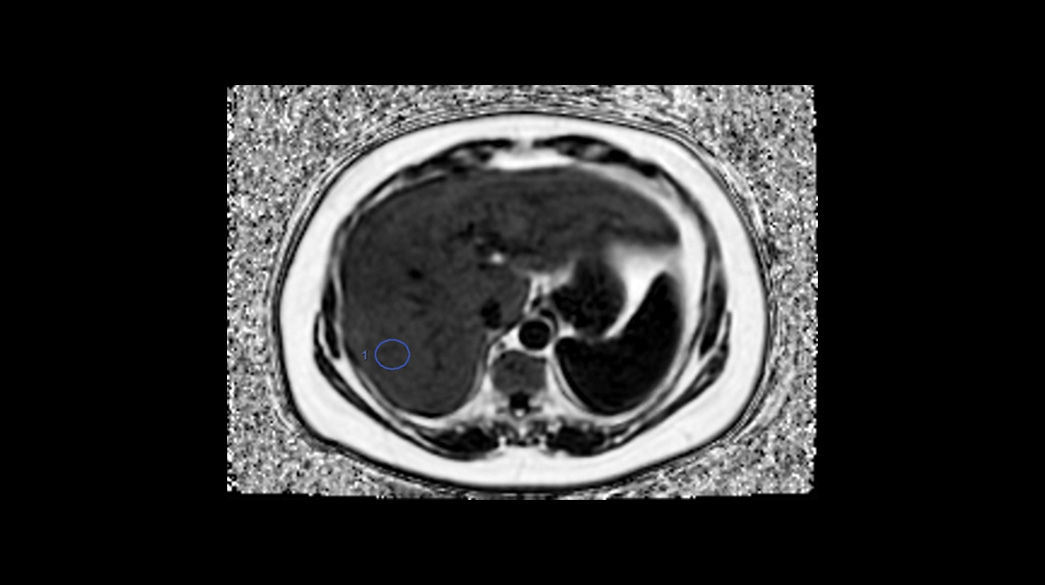

Body MRI for SIGNA™

Fast body MR imaging techniques to capture breast, abdominal and pelvic anatomy on any patient, with great flexibility.

Clinical Body MRI

Body MRI imaging applications